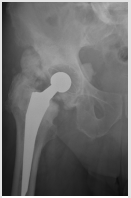

Male patient with 83 years of age, with history of total hip replacement 3 years ago, presenting HO Brooker III of the ipsilateral hip (Figure 1). He presented with pain and claudication. He underwent a single fraction of 750 cGy few hours before revision of the arthroplasty with substitution of the prosthesis on July of 2015. A 2D planning was done with AP-PA field toward the entire coxo-femoral joint (Figure 2). Treatment delivery was done on linear accelerator with photon energy of 18MV. Following treatment, patient experienced a significant improvement of his condition, with decrease on pain and regains the ability to do his daily activities by his own. On a radiograph taken 6 months after radiotherapy and surgery there are no signs of HO (Figure 3). Unfortunately he passed away three years later (July of 2018) of a mesothelioma diagnosed in 2017.

Figure 1: Right hip radiograph showing a Brooker III heterotopic ossification 3 years after total hip replacement.